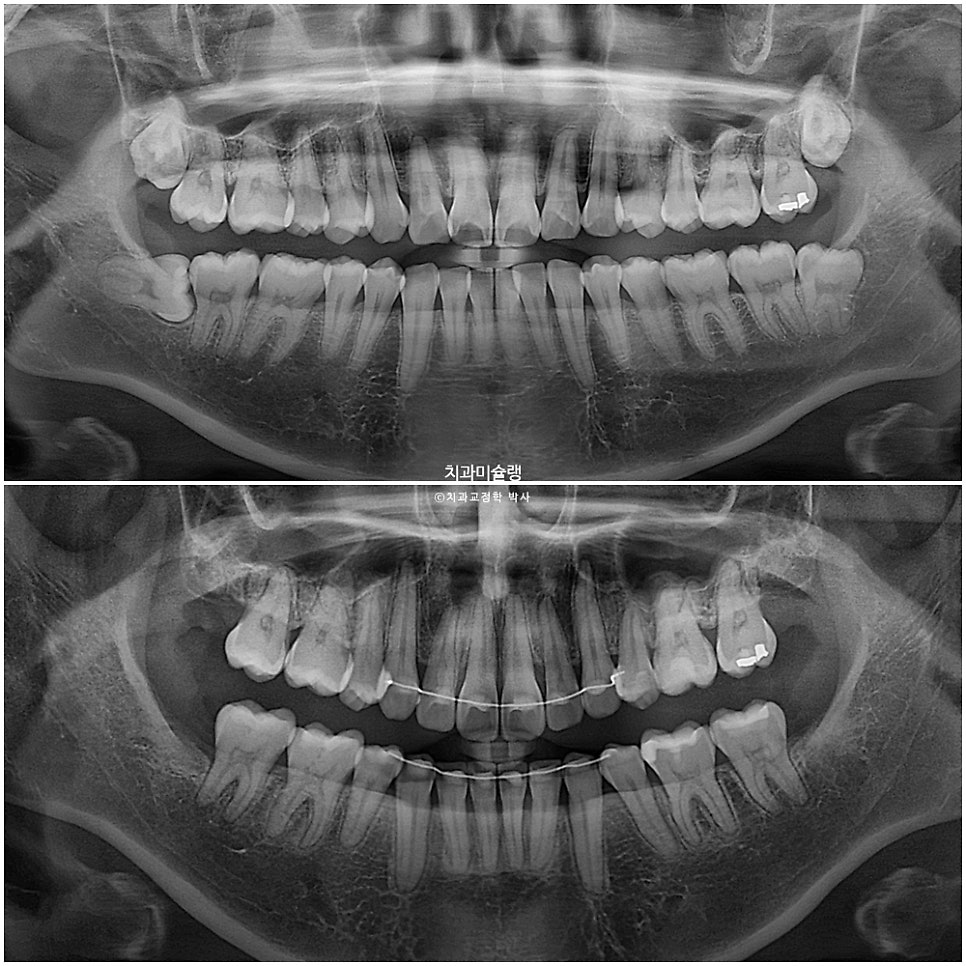

엑스레이로 보면 치근흡수는 없었으며 치아 뿌리 평행도는 좋습니다.

옆모습 엑스레이에서 앞니 각도의 개선이 확인됩니다.